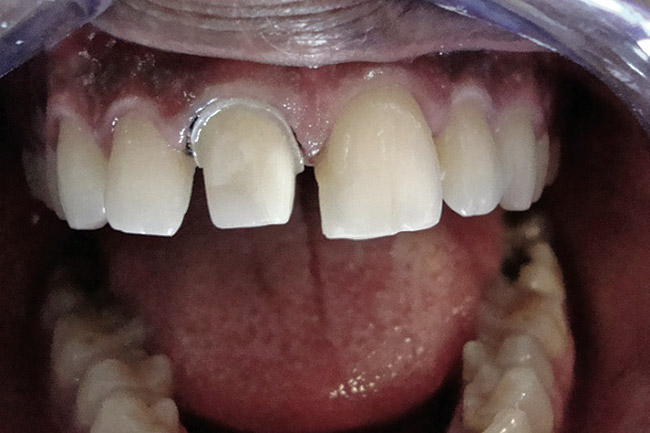

Figure 2  Caries extending cervically on upper right incisors.

Figure 2